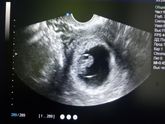

Итак, побывали мы с малышом на первом УЗИ! Очень переживала, как он там, ибо перенесла болезнь с высокой температурой и всеми вытекающими, очень боялась тонуса... Но, слава Богу, с креветочкой все отлично! Тонуса нет, отслоек нет, малыш полностью соответствует … Читать далее